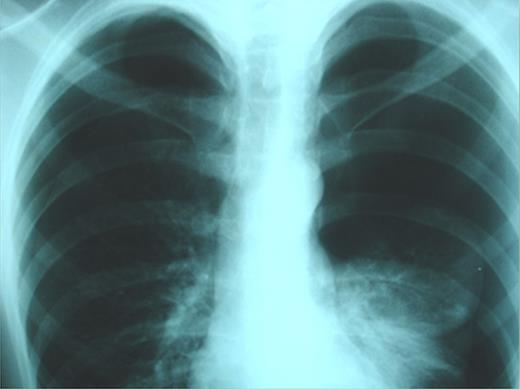

An otherwise-healthy, non-smoker, 20-year-old, overweight (BMI 29.8 kg/m2) Greek male patient was presented to the emergency department complaining of low-intensity chest pain and breathlessness of progressive worsening over the preceding 7 days. On admission, physical examination revealed diminished breath sounds on both sides. Blood pressure was 125/70 mmHg, heart rate 100 beats/min, SaO2 97% on air and axillary temperature 36.8°C. Laboratory tests were normal. Initial plain chest X-ray demonstrated bilateral pneumothoraces (more prominent on the left side) and no deviation of the trachea (Fig. 1).

Plain chest X-rays on admission revealing bilateral pneumothorax.